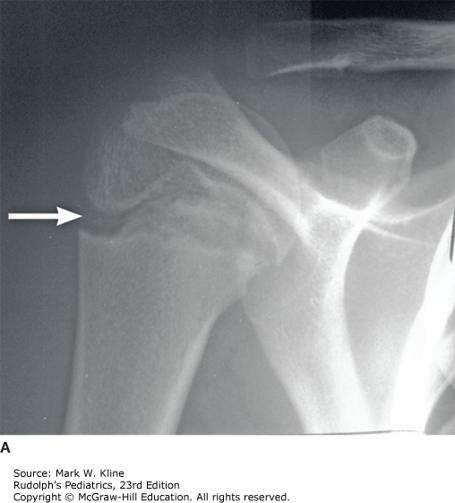

A 15-year-old boy presents to your office with insidious onset of right shoulder pain for the past 3 months. He is right-handed and denies any injury; however, he does play baseball. He plays pitcher on 2 teams, and sometimes he plays catcher as well. On exam, he has no shoulder asymmetry and mild tenderness of the proximal humerus. He has normal range of motion and strength. You obtain the radiograph as shown below. What is the most likely diagnosis?

A high volume of repetitive activity can stress tissue, including the growth plate in a growing adolescent. The radiograph shows widening of the proximal humeral physis, which is consistent with epiphysitis, or bone edema and growth plate injury. Epiphysitis can also be found at the medial epicondyle of the elbow in baseball pitchers. Radiographs can be normal, so a history of high levels of repetitive activities and activity-related pain should raise suspicion for growth plate stress injury. Treatment is rest from painful activities including throwing. Adhering to pitch count recommendations and rules is an important part of preventing these injuries.